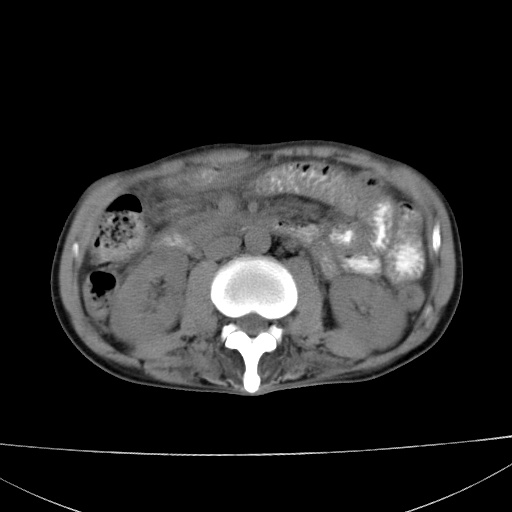

患者 男  41岁,右上腹痛伴腹泻10天,8年前有乙肝,本次b超查肝右叶占位来做ct ,请会诊!

肝硬化\\脾大\\门静脉高压,胃底静脉曲张可能性大.肝右叶肝癌肝内转移,建议增强.左侧小结石.

肝右叶肝癌肝内转移,建议增强

支持肝癌伴肝内转移,脾大,门静脉高压,胃底静脉曲张。

1)考虑肝癌;建议行ct增强扫描检查。2)脾大,门静脉高压,胃底静脉曲张。3)左肾小结石。

1)考虑肝癌及门脉瘤栓,建议行ct增强扫描检查。2)脾大,门静脉高压,胃底静脉曲张。3)左肾小结石。

结合病史;考虑肝癌。门静脉高压,脾大。胃底静脉曲张。

1)考虑肝癌;2)脾大,门静脉高压,胃底静脉曲张。3)左肾小结石。建议行ct增强扫描检查。